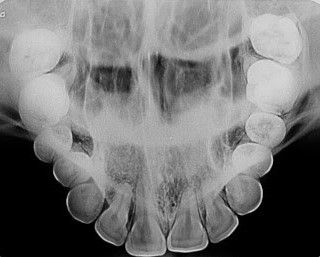

Radiografias intraorais